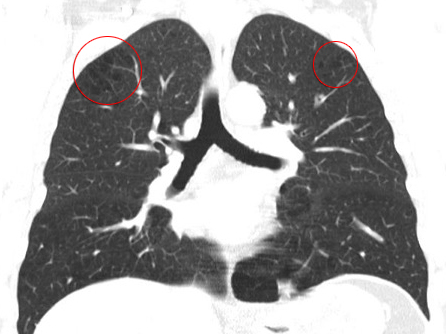

Den entscheidenden Hinweis brachte das von Doc Chris im Rahmen der Untersuchungen veranlasste Feinschicht-Computertomogramm der Lunge: Hier fiel ein sogenanntes bullöses Lungenemphysem auf. Darunter versteht man kleinste, feinwandige und sehr verletzliche Bläschen im Lungengewebe. Diese Bläschen sind luftgefüllt und können auch ohne Veränderung des Luftdrucks leicht platzen.

Das Blut ist nach jedem Tauchgang mit kleinen Stickstoffbläschen aufgesättigt, die von einer gesunden Lunge problemlos abgeatmet werden können. Finden sich aber Bullae in der Lunge, treten diese Stickstoffbläschen beim Platzen einer Bulla vom venösen Gefäßsystem direkt in den arteriellen Kreislauf über. Man spricht dann von einer arteriellen Gasembolie (AGE).

Bullae können im Rahmen einer chronisch obstruktiven Lungenerkrankung (COPD) entstehen. Langjähriger Tabakkonsum ist einer der Hauptgründe für eine COPD. Matthias hatte zwar schon vor drei Jahren das Rauchen aufgegeben, davor aber weit länger als 20 Jahre geraucht. In dieser Zeit hat sich bei Matthias ein bullöses Lungenemphysem, bestehend aus vielen kleinen Bullae, ausgebildet.

Die vermehrte Kraftanstrengung beim Flossen ausziehen nach dem Tauchgang hat, durch die damit verbundene Druckerhöhung im Brustkorb, ausgereicht, einige dieser kleinen Bläschen platzen zu lassen. Im Anschluss verstopften winzige Stickstoffbläschen wichtige Blutgefäße in Matthias Gehirn.